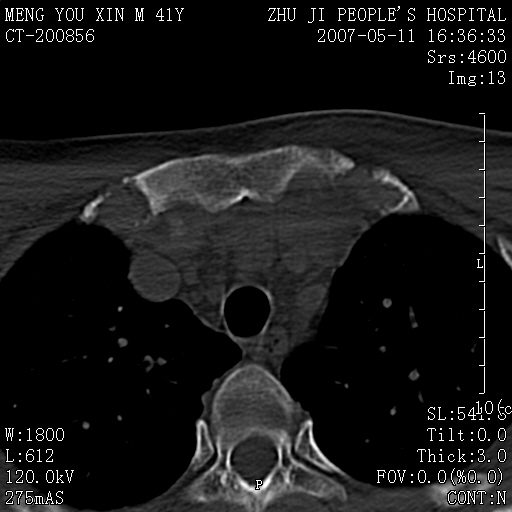

标题: CT8190:左锁骨胸骨端骨病,请会诊.

一周前左肩部酸痛,三天前颈部扭伤,后颈部摄片示颈椎病.现胸锁关节处肿痛明显.无发热.自诉三年前车祸安全气囊弹出.

双侧胸锁关节未见明显异常改变。

左侧锁骨近端膨大,骨皮质中断,并见少许骨膜反应,内见破坏,边缘见筛孔征,无硬化.因此考虑骨巨细胞瘤可能.

1,不支持结核,此例胸壁肿胀不明显,锁骨后方是局限性肿物而非脓肿,考虑为恶性肿瘤2,左侧锁骨近端膨大,骨皮质中断,并见少许骨膜反应,内见破坏,边缘见筛孔征,无硬化.因此考虑骨巨细胞瘤可能.